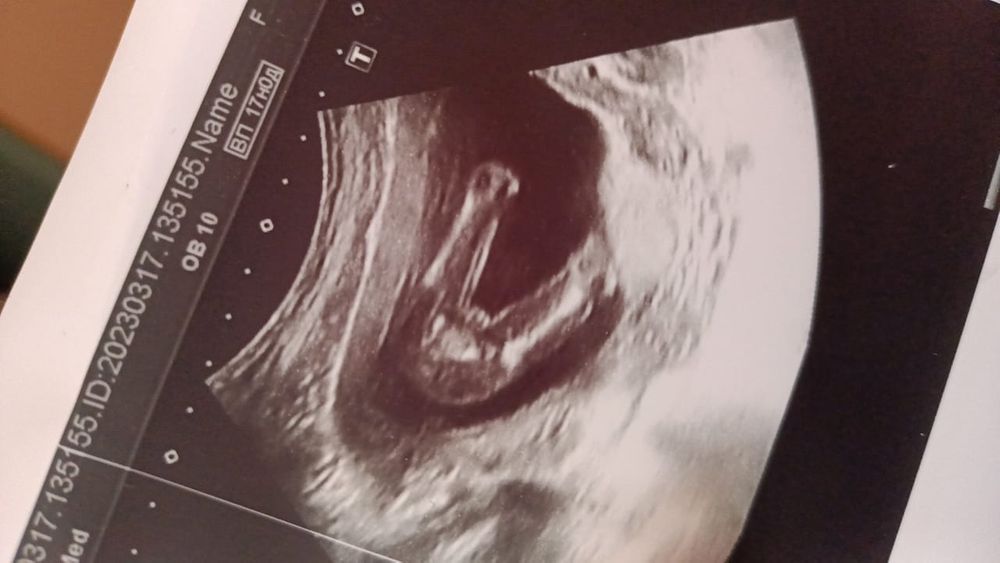

Снимок УЗИ, определение пола

Девочка конечно же 🤩

Девочка, у мальчика между ног торчит кое что)))

Кофейне зернышко между ног. Девочка)

А где делали УЗИ, платно или в ЖК? хорошая картинка, отчетливо видно, должно быть девочка) мне вчера в ЖК делали, ничего не увидели на таком же сроке, вроде аппараты в Москве хорошие везде стоят, но вот так